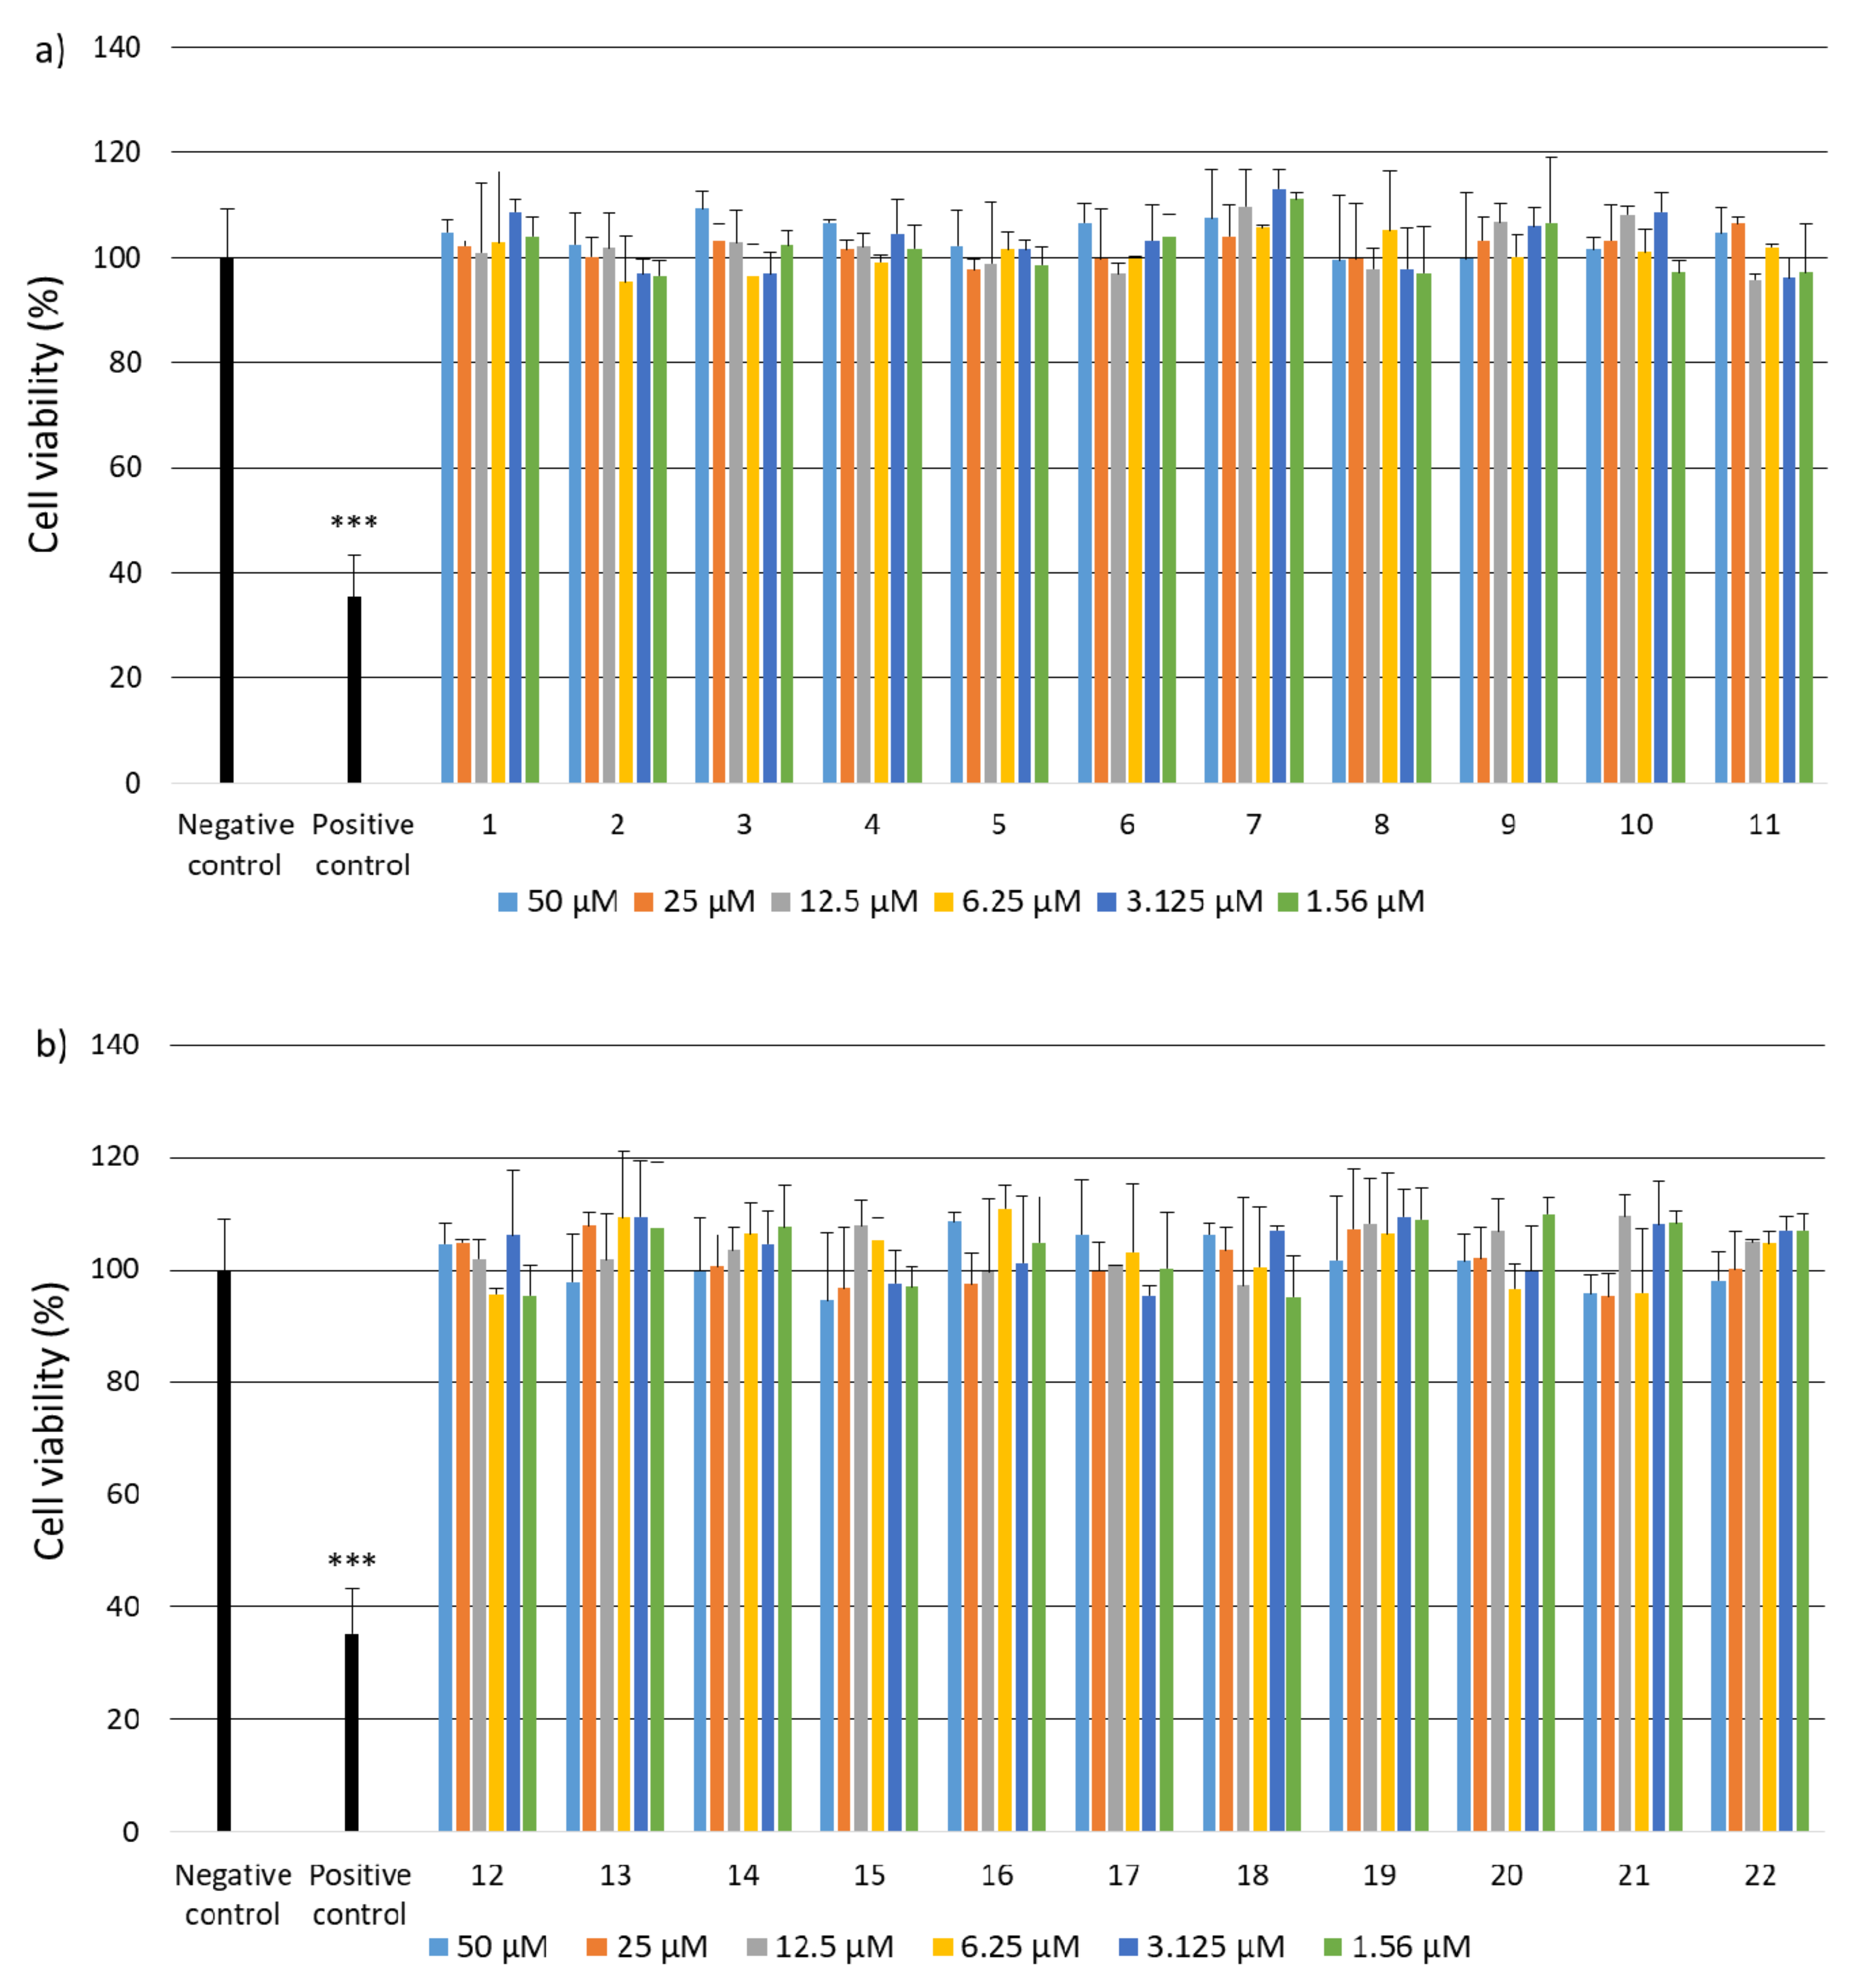

2.2. Research on Biological Activity of Collagen IV Fragments

3.7. Biological Activity Studies

- Cell Viability